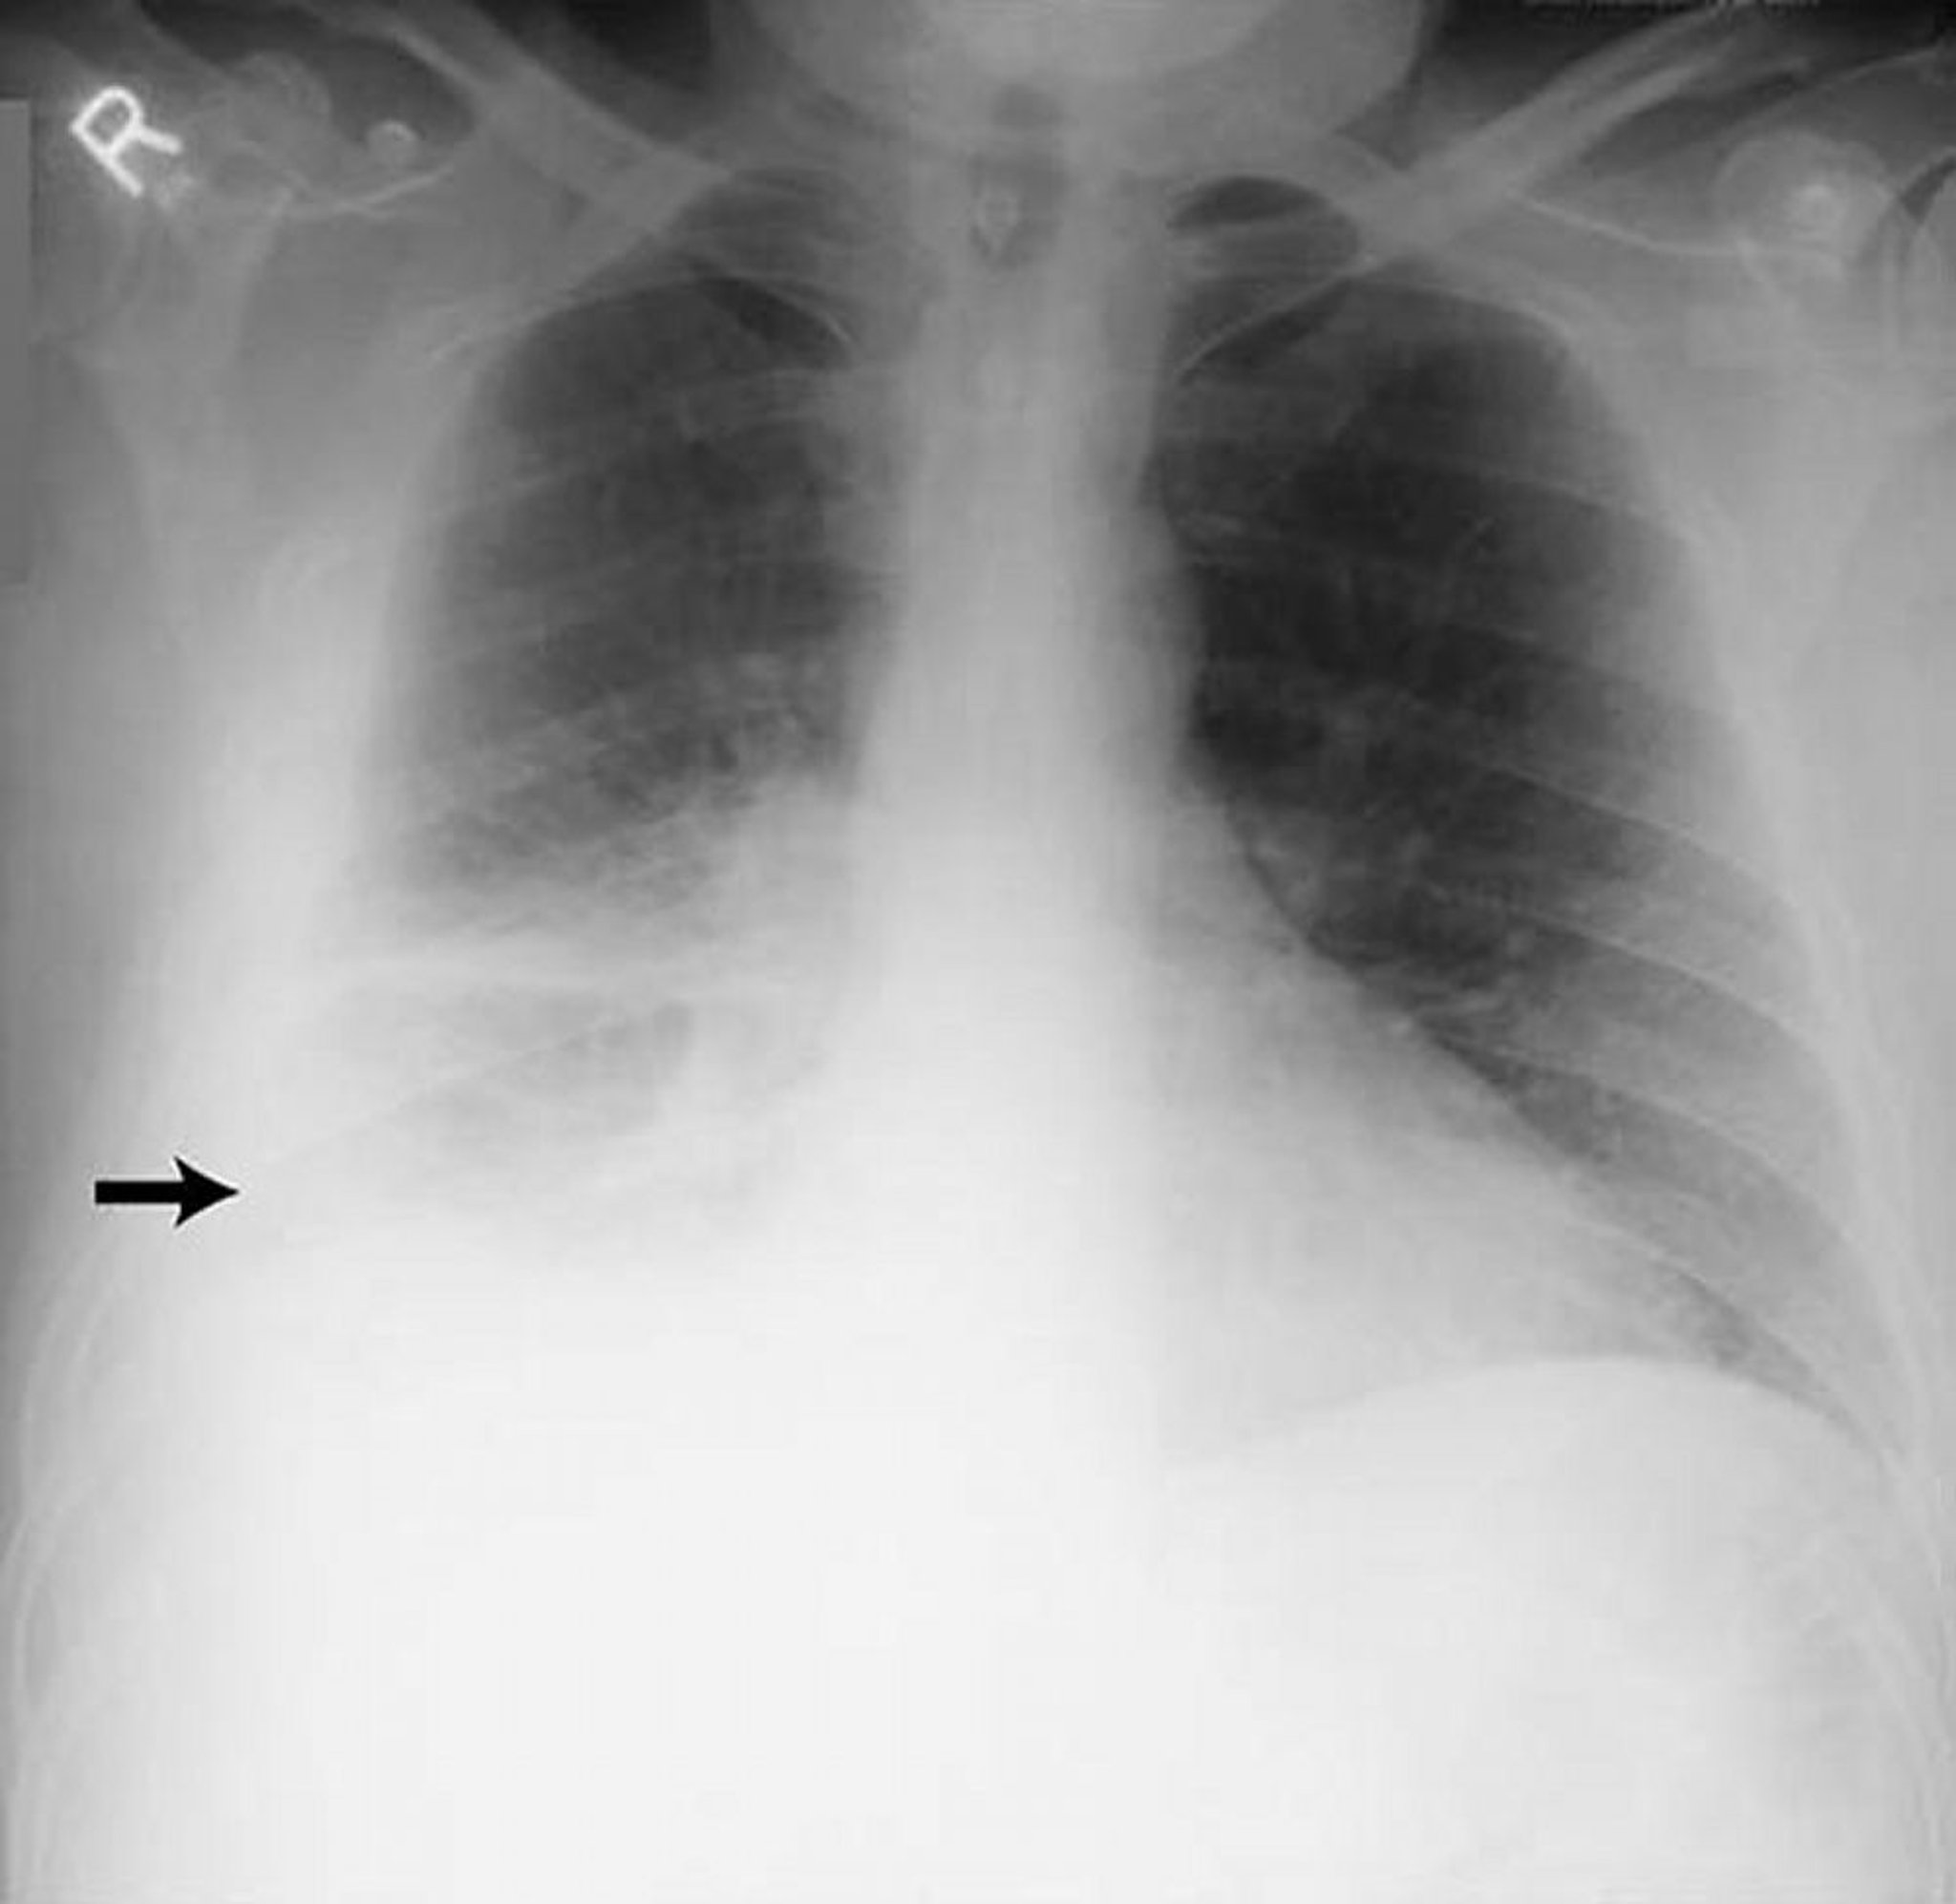

Tràn dịch màng phổi – Nhiều

Hình ảnh này cho thấy tràn dịch lớn ở màng phổi bên phải (mũi tên) trên bệnh nhân bị viêm màng phổi dạng thấp.

Được sự cho phép của nhà xuất bản. Theo Huggins J, Sahn S. Trong Bone's Atlas of Pulmonary and Critical Care Medicine. Biên tập bởi J Crapo. Philadelphia, Current Medicine, 2005.